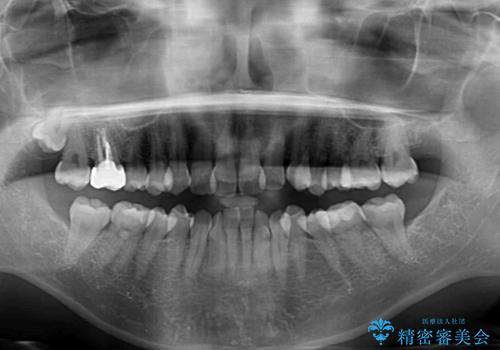

- 上下前歯のデコボコを気にして来院された患者様です。

デコボコは顕著であるものの、口元の突出感は強くないため、非抜歯にて矯正治療を行うこととしました。

元々の叢生と歯肉退縮傾向になる歯肉であったため、ブラックトライアングルが目立つことが想定されました。

治療過程でブラックトライアングル改善のため、IPR(歯と歯の間を削る)を活用しました。